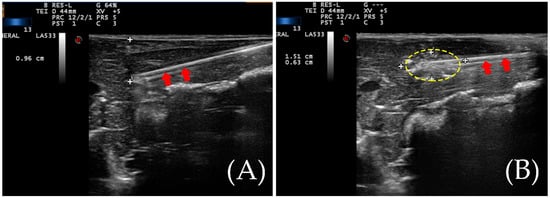

Figure 1. (A) An ablation needle was inserted during RFA. The tip of the ablation needle is about one centimeter from the liver surface. The red arrows indicate the ablation needle rod. (B) The yellow dotted circle indicates the vaporization zone during the ablation.